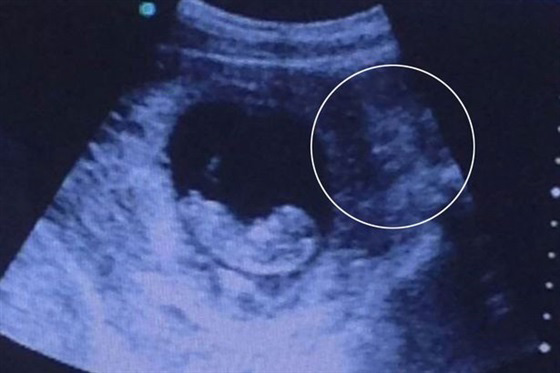

تظهر صورة في البداية وكأنها صورة تذيب القلوب لطفل لم يولد بعد يستريح بهدوء في رحم والدته، لكن عند تدقيق النظر يظهر شئ تقشعر له الأبدان. ذهبت صورة كالفيروس على الإنترنت لكائن غريب بجوار جنين بعد تسجيل لقطات له خلال فحص بالموجات فوق الصوتية. حققت الصورة أكثر من 979 ألف مشاهده منذ تحميلها أمس على الموقع، حيث انقسم مستخدمو مواقع التواصل الإجتماعى في تحديد ماهية هذا الكائن الغريب، فجاءت أغلب التعليقات بين إنه إله هندوسى، وحورية بحر، وشيطان. لم تكن هذه المرة الأولى التي يظهر فيها أشكال غريبة بجانب الأجنة، فقد ظهر من قبل شكل جد متوفى يقبل جنين بعد إجراء مسح4D.